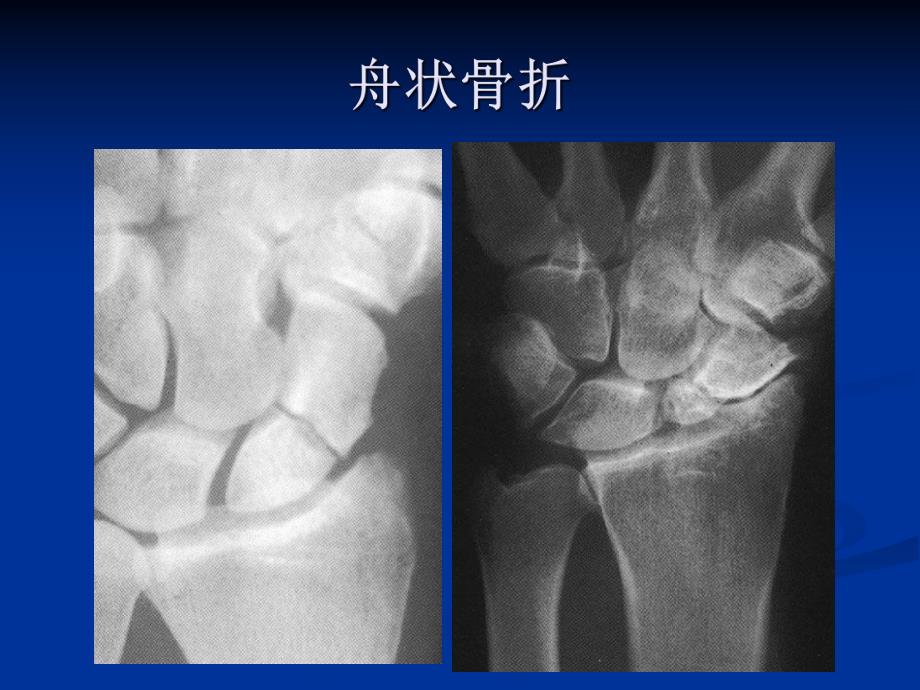

1.结节部结节部2.远端关节远端关节面面 3.远端远端 1/3 4.腰部,中腰部,中 1/35.近极部近极部无移位或很小移位的骨折无移位或很小移位的骨折(mm)注意隐匿性骨折的处理注意隐匿性骨折的处理前臂或上臂石膏固定前臂或上臂石膏固定直到骨折愈合直到骨折愈合(一般一般8-12周周)